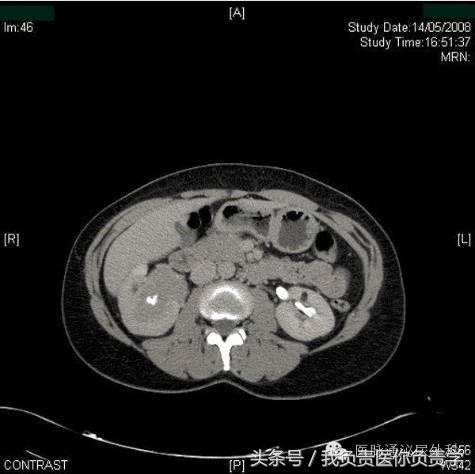

CT尿路造影的轴向图像以及相关的矢状重建,显示右肾盂中存在大面积充盈缺损。充盈缺损延伸并占据右肾盂中多数空间,造成肾造影显影期质量效应和肾脏增强的相对延迟(图2,3)。放射学表现和无痛性血尿及尿液细胞学阳性共同指示上尿路上皮癌。

图2

图3

在该病例中,经患者同意进行了膀胱镜检查,结果显示膀胱正常,未见任何外生肿瘤。CT尿路造影时发现右肾盂中的大面积充盈缺损结合尿细胞学检查阳性,将该患者确诊为上尿路上皮癌。